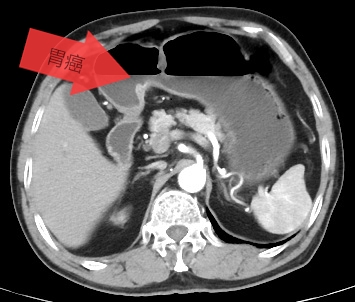

我院影像科从2018年开始,利用CT、MR分辨率高、成像方法多的特点,开展胃肠快速充盈低张CT、MR检查技术,通过多序列、多窗位、多方位检查,对肠壁、及其腔内腔外病变连续观察,取得了很好的检查诊断效果。检查技术成熟安全、无创,确诊了多例胃癌、胃息肉、结肠癌、肠先天性发育旋转不良等胃肠道疾病,并对肿瘤的转移及周围结构进行评估,为患者进一步综合治疗,打下了坚实的基础。

胶囊内镜检查具有移动的不可控性,常规消化道纤维内镜存在视野局限、有创,通过障碍无法评估腔外解剖与病变,对通过障碍的病灶仅能显示病变近端,然而胃肠道快速充盈低张影像检查技术具有无创、反复观察、定位准确的优势。它可通过充分的肠道准备,虚拟内镜及多方位重建,可从任意角度和方式对病灶进行观察,并能从狭窄、梗阻处两端观察肠腔的解剖和病变,可靠的显示了病变部位和范围,同时提供腔内外的情况并能对淋巴转移、血管癌栓、远处转移进行评估。

影像图片(二)